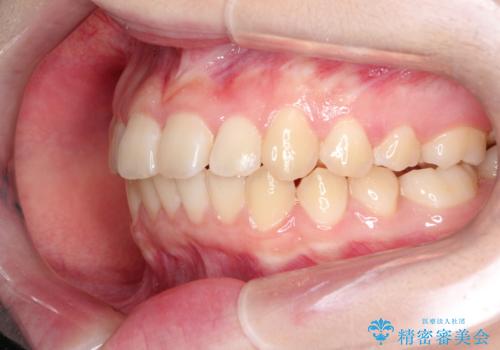

なるべく通院回数を減らして矯正したい インビザラインでのガタガタ矯正

ワイヤー矯正が1か月に1回程度来院が必要なのと比較すると、2-3か月に1回の来院でもよいので(症例によります)、通院回数を減らすことができて、患者様の負担を減らすことができます。